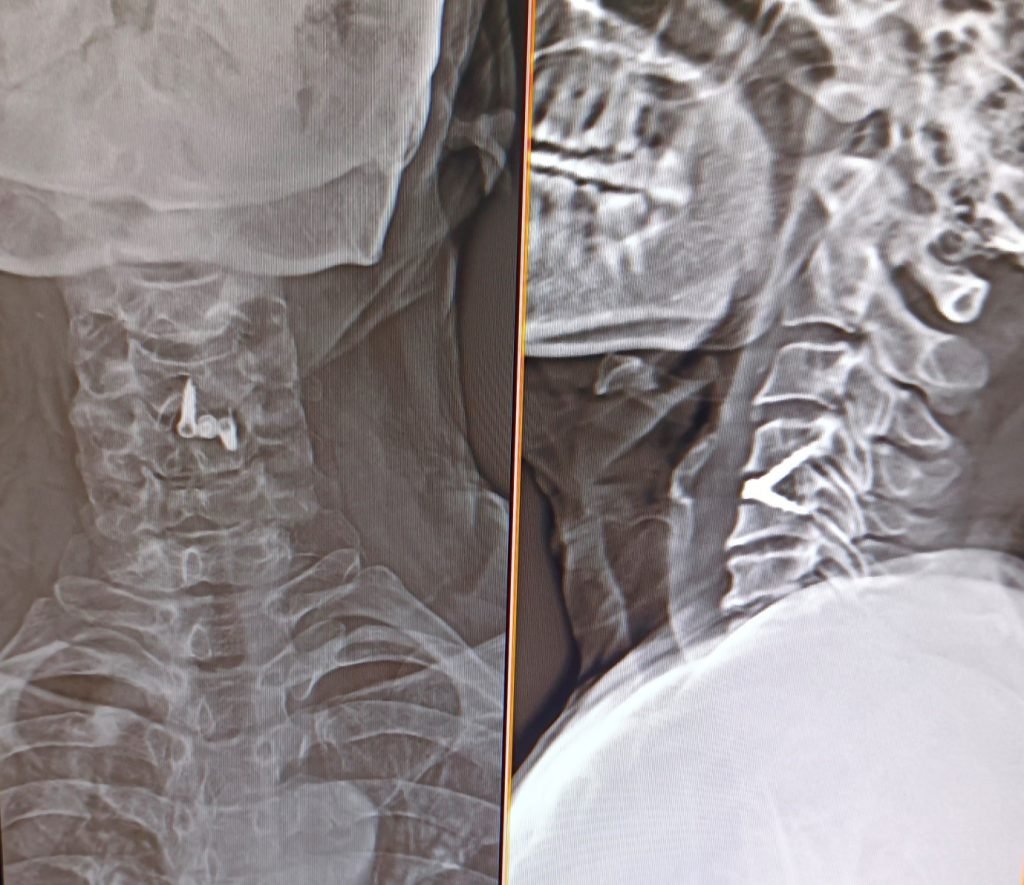

Condition:

Cervical disc prolapse in which the herniated disc compresses the nerve roots and spinal cord, often associated with spinal cord edema.

Treatment:

Anterior Cervical Discectomy and Fusion (ACDF) – The damaged disc is removed and the spine is stabilized using a bone graft or implant to relieve pressure on the spinal cord and nerves.